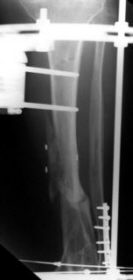

A 42 year old lady sustained a severe comminuted fracture of her right tibia in a road traffic accident.

The fracture was treated with a 3 ring Sheffield Hybrid Fixator. 3 compressive olive wires were inserted across the diaphyseal fracture site using the middle ring and 2 wire slider units. The pilon fracture was reduced with olive wires. Union was uneventful.